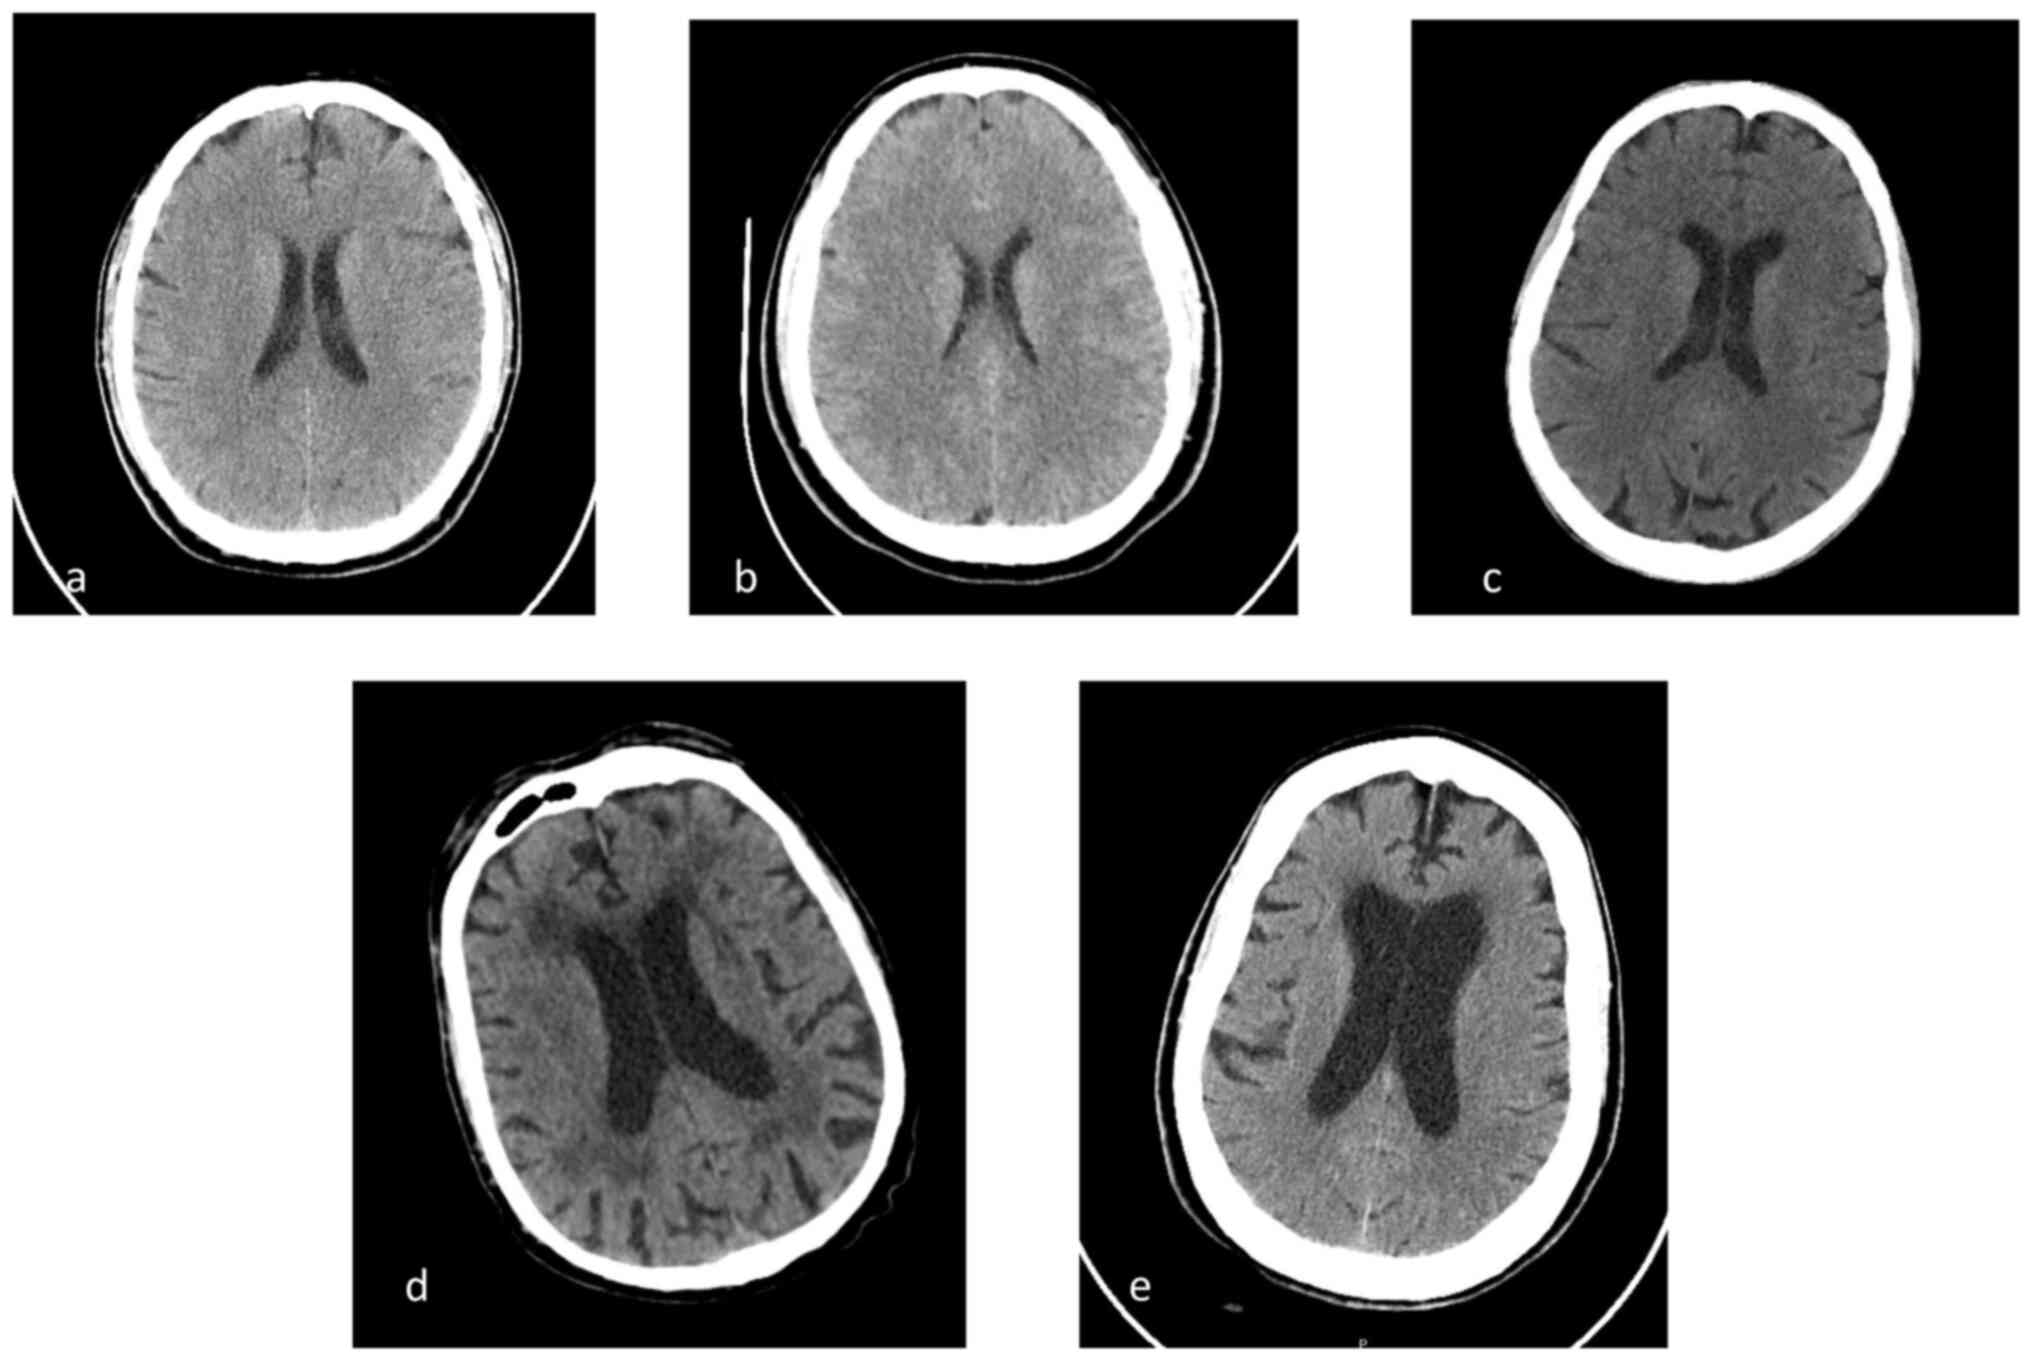

Figure 1

Patients' head CT scan. CT scans of the (a) first, (b) second, (c) third, (d) fourth, and (e) fifth patients' head.

A head CT scan (SOMATOM® Definition Flash scanner, Siemens AG) showed no abnormalities (Fig. 1A). Cerebrospinal fluid (CSF) examination revealed high protein levels (4,175 mg/l; normal range 150-450 mg/l), high lactate dehydrogenase levels (193 IU/l), reduced glucose levels (18 mg/dl), and hypercellularity (152 cells/mcl mostly lymphocytes; normal range <5 cells/mcl). Empirical treatment with ceftriaxone 2 g twice daily, acyclovir 10 mg/kg three times daily, and corticosteroids (dexamethasone 4 mg three times daily) was initiated. Molecular biology [reverse transcription (RT)-PCR] for Listeria detection was performed using a FilmArray Meningitis/Encephalitis Panel (ME) CE-IVD according to the manufacturer's protocol (cat. no. RFIT-PRT-0005, BioFire Diagnostics, LLC) on the CSF, and the results were positive for L. monocytogenes, which was confirmed by CSF culture [performed in 5% blood agar with Brain Heart Infusion (BHI) to enhance recovery of Listeria isolates with incubation in aerobic conditions at 37˚C for 24 to 48 h]. Targeted therapy was established with intravenous (i.v.) ampicillin 3 g every 6 h, and gentamicin 400 mg i.v. Dexamethasone 4 mg three times a day was also maintained.

Laboratory tests revealed elevated WBC counts (13,300/mm3, 73.3% neutrophils), high CRP levels (28.91 mg/dl), and elevated transaminase levels [aspartate transferase (AST) 314 IU/l; alanine transferase (ALT) 116 IU/l]. A head CT scan was normal (Fig. 1B).

Head CT scan was negative (Fig. 1C). CSF analysis showed 1,364 leukocytes/µl with a preponderance of lymphocytes. CSF protein levels were 420 mg/l, and the glucose level was 32 mg/dl (blood glucose, 98 mg/dl).

Blood tests revealed elevated CRP levels (18 mg/dl), reduced WBC counts (3,500/mm3) with normal formula, mild anemia (11.3 g/dl), and normal PCT levels. A head CT scan showed no abnormalities (Fig. 1D).

Neurological examination revealed neck stiffness with positive Kernig's and Lasegue's signs. Laboratory data showed high WBC counts (5,600/mm3, 76% neutrophils), high CRP levels (36 mg/dl), creatinine 2.1 mg/dl (eGFR with CKD-EPI 31 ml/min), AST 56 IU/l, ALT 41 IU/l, and glucose 176 mg/dl. A head CT scan was normal (Fig. 1E).

Two of the patients reported on in this study were healthy and immunocompetent men who were not involved in farming or animal husbandry. We consider as ʻimmunosuppressedʼ every patient with impaired immunity or an impaired immune response due to congenital or acquired disease or those patients who took drugs that can induce an impaired immune status (e.g. chemotherapy, chronic corticosteroid administration). The third patient was immunosuppressed due to chronic corticosteroid treatment but reported no contact with animals or unknown foods prior to infection. The fourth patient had a history of hematologic disease; the fifth patient was affected by CKD due to diabetes, which could be considered an immunosuppressive disease, and reported multiple respiratory infections previously. None of them had a clear exposure to foods classically associated with an increased risk of Listeria infection (1). None of them were HIV positive, as performing an HIV test is strongly suggested in the presence of Listeria meningeal infection (13,14), nor were they HCV or HBV positive (15-17). It is hypothesized that they were asymptomatic intestinal carriers since the incidence of fecal carriers is estimated to be 1-10% of the population (11,18). In addition, head CT scans of all patients described did not reveal signs of rhombencephalitis. Perhaps, MRI would have been a better method to address this issue, but it was not performed due to the patients' serious clinical conditions.